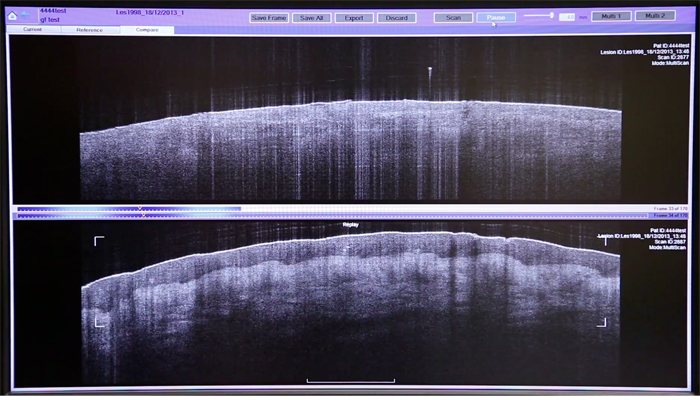

VivoSight is a point-of-care tissue-imaging system that for the first time allows users to see below surface of the skin.